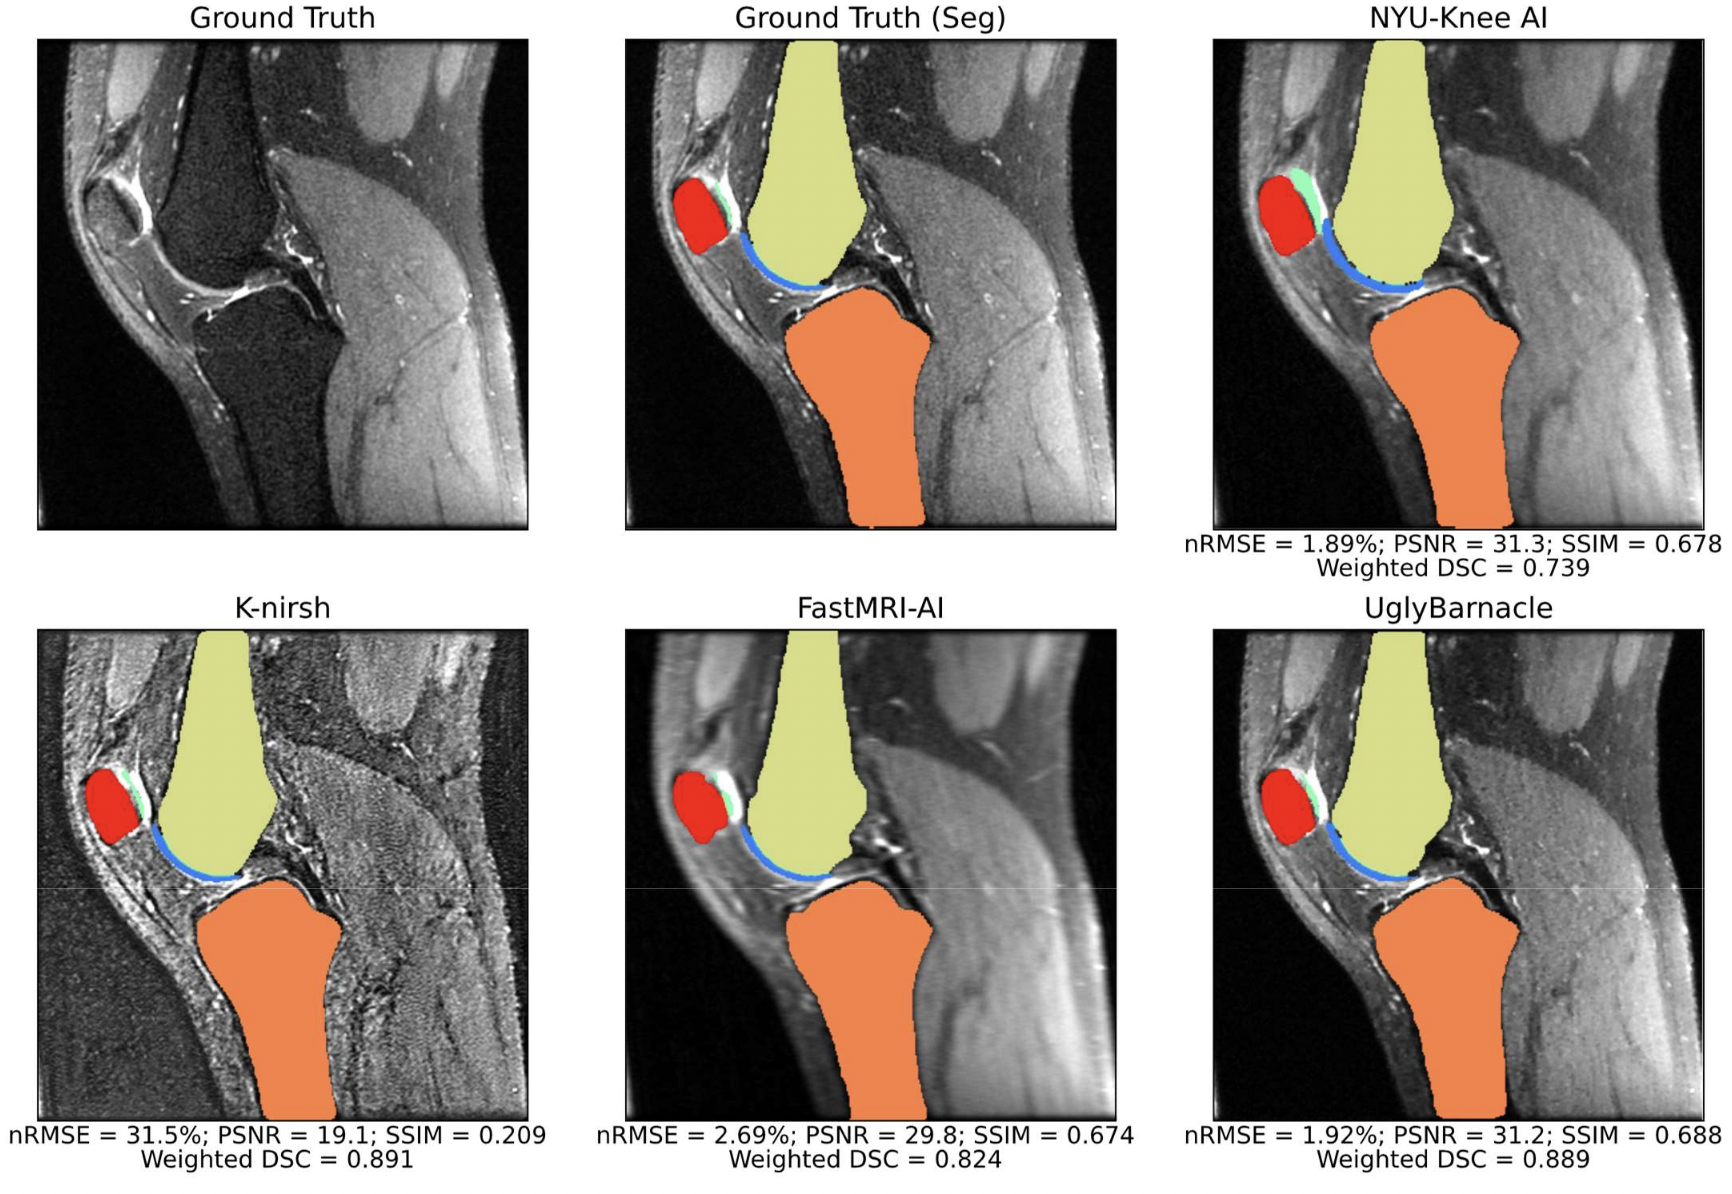

K2S Challenge: From Undersampled K-Space to Automatic Segmentation

Aniket A. Tolpadi, Upasana Bharadwaj, Kenneth T. Gao, Rupsa Bhattacharjee, Felix G. Gassert, Johanna Luitjens, Paula Giesler, Jan Nikolas Morshuis, Paul Fischer, Matthias Hein, Christian F. Baumgartner, Artem Razumov, Dmitry Dylov, Quintin van Lohuizen, Stefan J. Fransen, Xiaoxia Zhang, Radhika Tibrewala, Hector Lise de Moura, Kangning Liu, Marcelo V. W. Zibetti, Ravinder Regatte, Sharmila Majumdar, Valentina Pedoia

Bioengineering, 10, 267 (2023)

journal URL